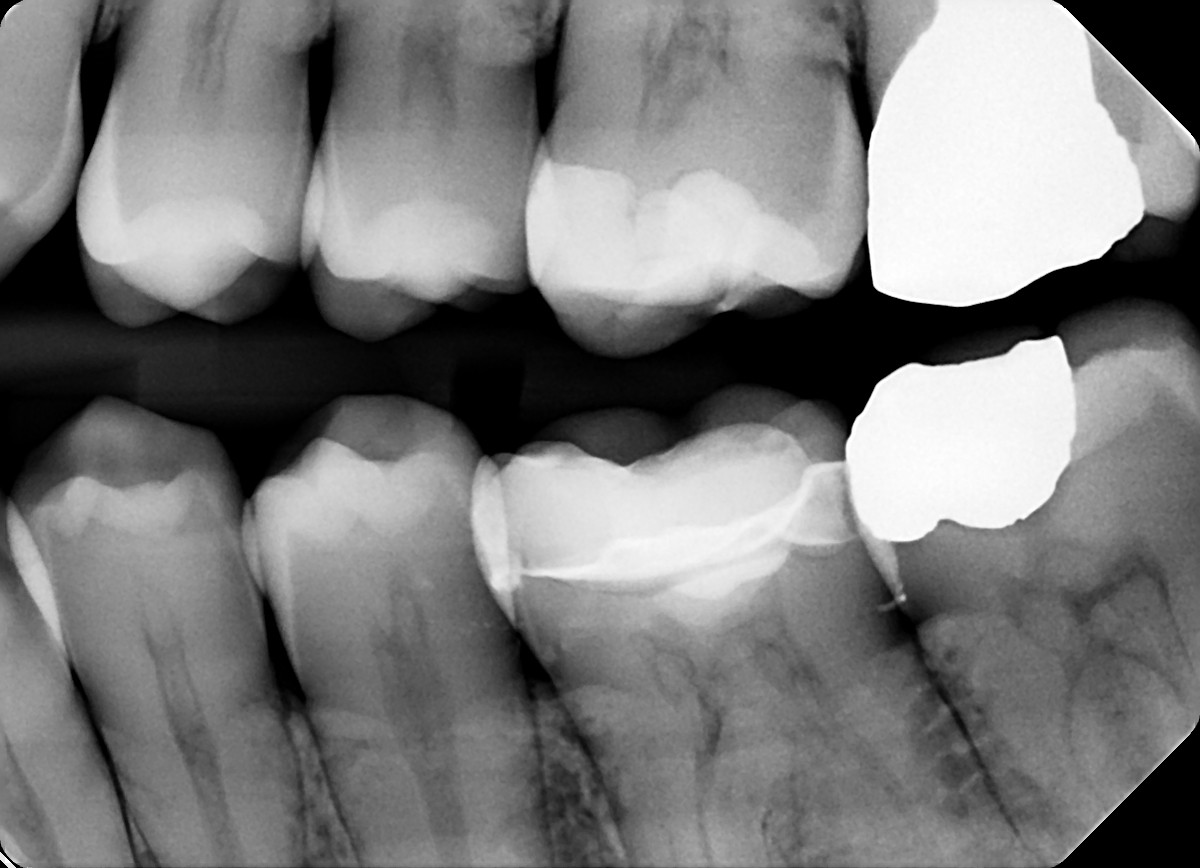

1. On which surface a recurrent caries can be detected?

2. On which surface a recurrent caries can be detected?

3 / 35

mesial tooth # 3.7 is CBO